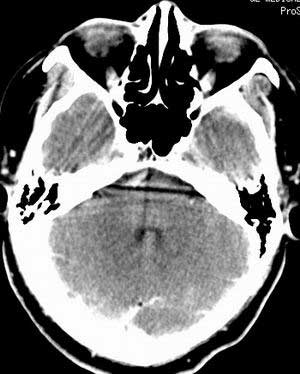

患者男,58岁。耳爆震伤后耳聋2年余,而后双耳道肿胀,间断性流脓。近一月来头痛、恶心、呕吐,右眼红痛,不能入眠。

在平扫时,见右侧枕骨下方小脑半球表面带状模糊稍高密度影,考虑为耳源性脑内感染。

双侧乳突蜂房密度呈气体样,慢性乳突炎可能性不大,

双侧颞叶脑实质密度均匀未见异常密度灶,

平扫右侧岩骨与枕骨交角内侧脑质内见淡片状密度增高影,内缘清晰。增强图象上未见明显显示。

考虑:1)伪影可能,建议复查头ct平扫。

2)加照头ct骨窗,以显示乳突气房内是否有病变。

右枕颅骨内板下高密度应该是窦的变异,和其症状应该无关,根据病史另找原因吧。[em16]

条状高密度为小脑幕吧

条状高密度为小脑幕

横窦乙状窦。

增强的横窦乙状窦。